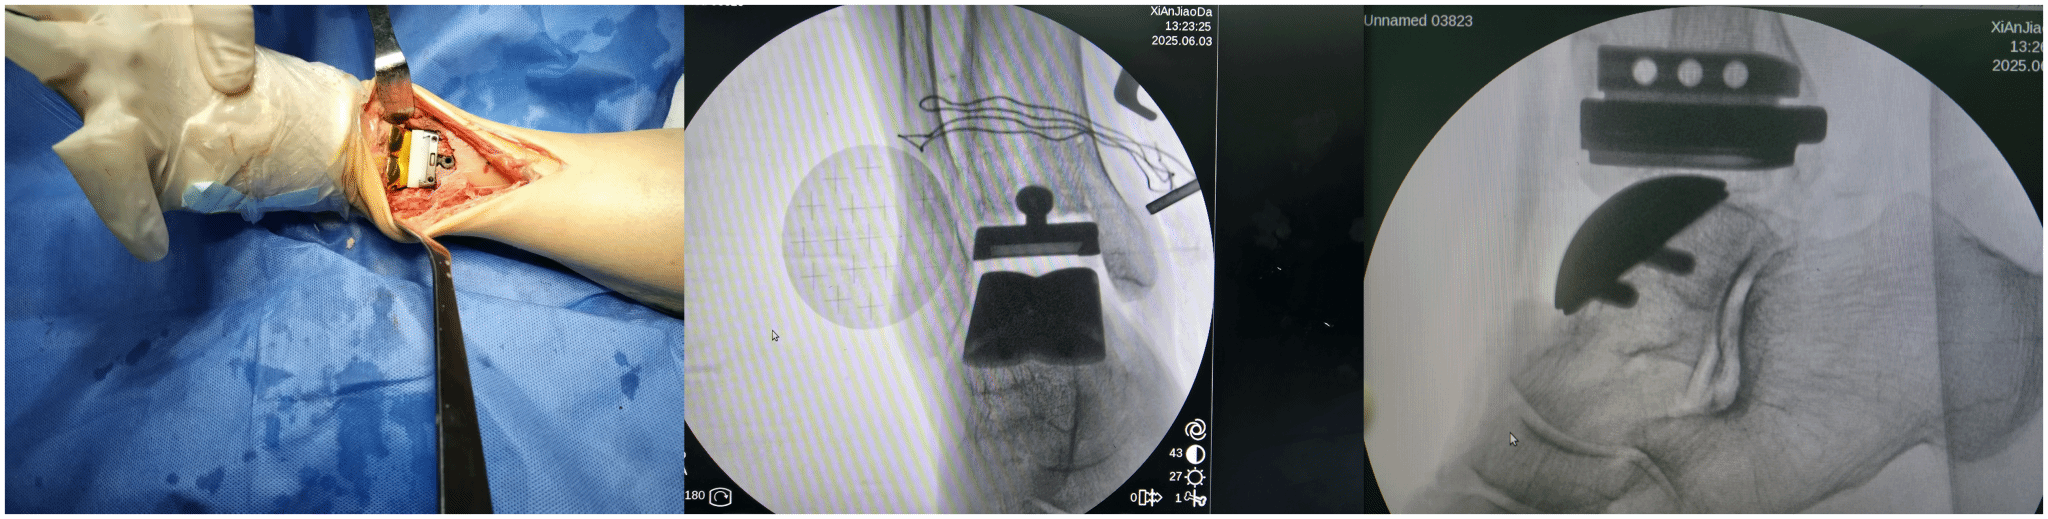

杨佩团队根据张女士的病情,为她进行踝关节CT数据进行三维重建,在虚拟空间中反复模拟、精心规划,找到她最佳截骨方案和假体安放位置。紧接着,团队将最优方案转化为3D打印的个性化手术导板,严丝合缝地贴合患者自身的骨骼轮廓,做到量身定。手术中,导板的应用显著减少了依赖经验判断和反复X光透视调整的需要。这不仅意味着更精准的操作、更小的创伤、更短的恢复期,手术时间缩短,也减轻了患者的焦虑。